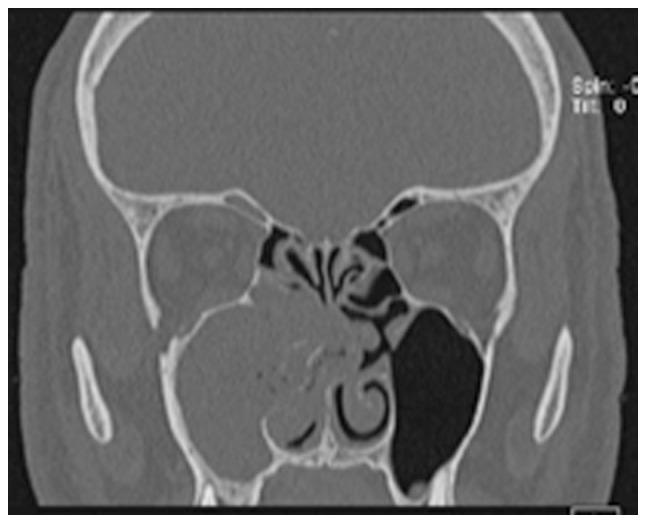

There are numerous types of sinusitis caused by fungal strains, some of which already colonize the nasal cavity. Mild forms present fungus balls growing inside a preexisting sinus cavity. The invasive type ranges from chronic manifestations to acute aggravated episodes. The latter scenario is encountered in cases with reduced immune responses, such as patients with diabetes, individuals receiving any form of transplant, AIDS cases and chemotherapy patients. Without the control of immunosuppression, the infection is aggravated and extends to the orbit and inside the skull base, regardless of the prompt surgical and medical treatment. This is the most common pathogenic fungus on the nasal sinuses level. It can occasionally enter the sinus cavity during dental procedures. The pathogenesis is enhanced by anaerobic conditions in poorly ventilated sinus cavities. Rhinosinusal aspergilloma has a slow, insidious evolution over months and even years. Our experience revealed the presence of both a dental problem and previous self-administered antibiotic regimens in almost every case. The initial symptoms are common with sinusitis of dental origin, but aspergilloma should be considered when a patient with a competent immune system does not respond to standard antibiotic treatment. The final diagnosis of rhinosinusal aspergilloma is conducted on a pathology sample with silver staining. The bacteriology exam of the sinus secretion rarely reveals a fungus infection; however, as revealed in our clinical experience, there may be coinfection with other multidrug-resistant bacteria. Surgical treatment must establish a wide exposure of the sinus cavity and correct drainage regardless of the external, combined or endoscopic approach. Early diagnosis and emergency surgical debridement along with administering systemic antifungal compounds in some cases represent the key to the successful treatment of invasive aspergilloma.

由真菌菌株引起的鼻窦炎有多种类型,其中一些已经在鼻腔定植。轻度形式表现为在已有的鼻窦腔内生长真菌球。侵袭性类型从慢性表现到急性加重发作不等。后一种情况见于免疫反应降低的病例,如糖尿病患者、接受任何形式移植的个体、艾滋病患者和化疗患者。如果不控制免疫抑制,无论进行及时的手术和药物治疗,感染都会加重并蔓延至眼眶和颅底。这是鼻窦层面最常见的致病真菌。它偶尔会在牙科手术过程中进入鼻窦腔。通风不良的鼻窦腔内的厌氧条件会增强其发病机制。鼻窦曲霉菌瘤在数月甚至数年的时间里缓慢、隐匿地发展。我们的经验表明,几乎每个病例都存在牙齿问题和先前自行使用抗生素的情况。初始症状与牙源性鼻窦炎常见症状相同,但当免疫系统正常的患者对标准抗生素治疗无反应时,应考虑曲霉菌瘤。鼻窦曲霉菌瘤的最终诊断通过银染色的病理样本进行。鼻窦分泌物的细菌学检查很少能发现真菌感染;然而,正如我们的临床经验所示,可能会合并其他多重耐药菌感染。无论采用外部、联合还是内镜方法,手术治疗都必须广泛暴露鼻窦腔并建立正确引流。早期诊断、紧急手术清创以及在某些情况下使用全身性抗真菌药物是侵袭性曲霉菌瘤成功治疗的关键。